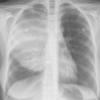

Lymphoma -Mediastinal and left axillary nodes (see CT)

Date: 04/01/2014

Views: 2580